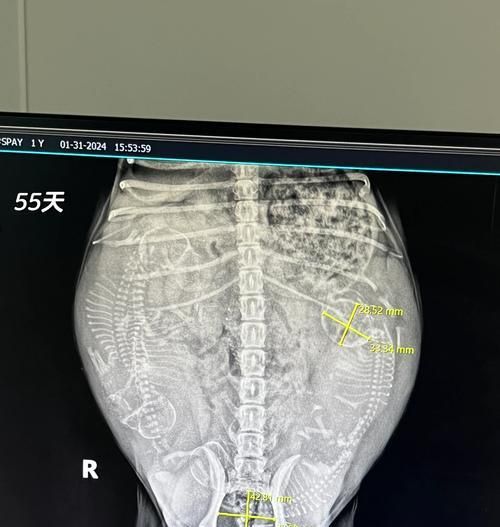

八:定期进行产前检查

在怀孕期间,定期带哈士奇去兽医那里进行产前检查非常重要。兽医可以通过超声波等方式检查胎儿的发育情况,确保母狗和胎儿的健康状况良好。